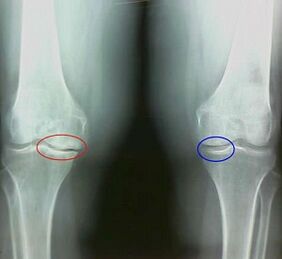

For example, what is the difference between arthritis and arthrosis of the knee joint?In arthritis, the synovial shell of joint tissues occurs.This leads to an increase in the temperature in the joint.

The joint swells, a persistent pain syndrome develops and increases during movement.In the case of osteoarthritis, the pain only occurs after physical activity, you can hear a characteristic crunch or clicks in the joint, the joint is gradually deformed and loses mobility.

Osteoarthritis gradually develops and is not strange in the early stages.It is often taken for physical tiredness.The chronic form of arthrosis is also referred to as osteoarthrosis.The answer is obvious about what is worse - osteoarthritis or osteoarthritis.The last option is a result of the development of osteoarthritis and its acute form.

The following are differentiated under the symptoms of arthrosis:

- After physical activity, pain occurs with sudden movements, curves, inclinations, after calm, pain;

- A characteristic crisis in the joints has been determined;

- The pain after a long calm, which runs within 15 to 20 minutes of mobility (this is associated with the stagnant phenomena that occur in the joint);

- The connection is deformed, its mobility decreases.